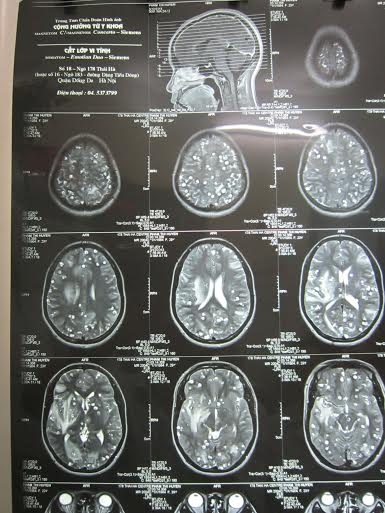

| Những nốt tròn trong có nhân là nang sán lợn làm tổ dày đặc trong não bệnh nhân. Ảnh: BS cung cấp. |

Ông đến Viện Sốt rét-ký sinh trùng-côn trùng TW khám thì biết mình bị nhiễm ấu trùng sán lợn. Ấu trùng làm tổ trong não đè vào dây thần kinh thăng bằng nên ông hay chóng mặt, đau đầu. Ông được điều trị từ năm 2012 đến nay.